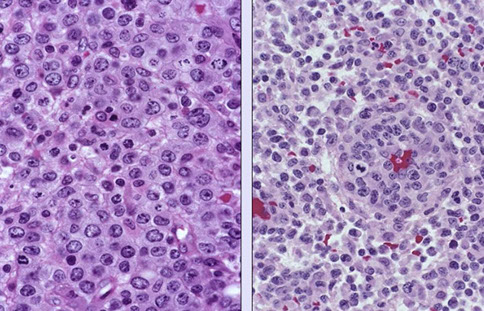

Anaplastic large cell lymphoma (ALCL), ALK positive

Anaplastic large cell lymphoma (ALCL), ALK negative